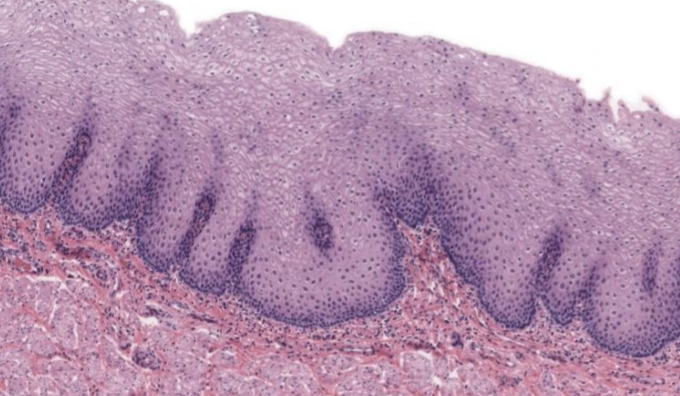

Clasifique tejido epitelial

urotelio

Indique sitio anatómico donde se encuentra

vejiga